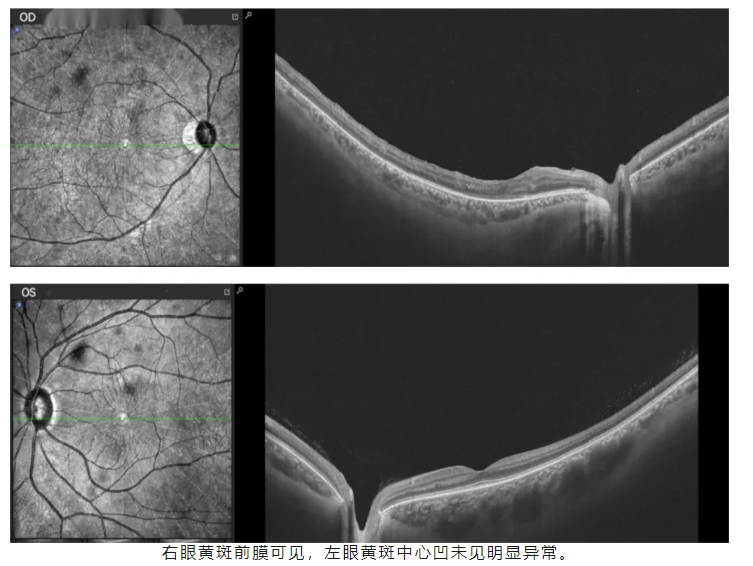

黄斑OCT和HRA-OCT

(3)右眼黄斑前膜

专科检查、前节OCT检查及B超检查提示,右眼视网膜复位术后状态,晶状体颞侧楔形混浊,且存在鼻侧后囊及皮质缺失,但前囊完整。基于其复杂的眼部手术史及后囊局部缺失,手术方案设计如下:

在本次病例中,术前检查显示晶状体已完全混浊。前节OCT检查表明后囊存在缺损,而B超提示“右眼颞下方玻璃体腔可见环形强回声影,后极部视网膜略增厚”,散瞳后发现部分晶状体落入玻璃体腔。基于这些检查结果,我们采用了飞秒辅助的phaco+IOL+玻切术。由于患者存在后囊缺损,术中采用“IOL前囊夹持”技术,将IOL的光学部分夹持在前囊口后方,利用前囊膜来固定IOL。